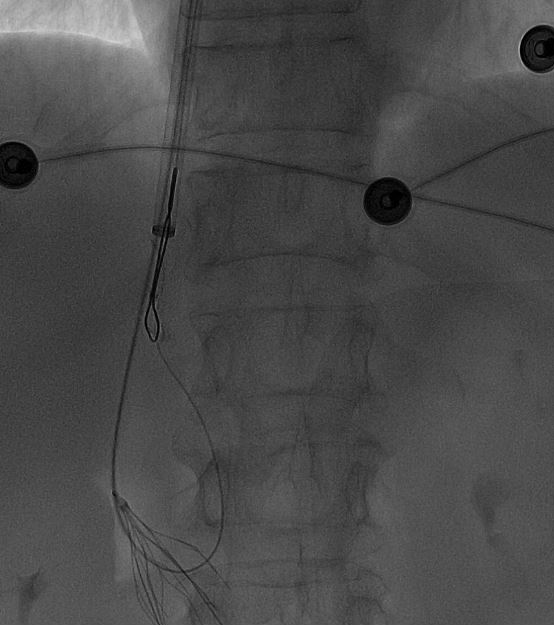

一切准备就绪后,田轩带领介入诊疗团队为阿婆实施下腔静脉滤器取出术。

术中,团队在影像设备的精准引导下,娴熟操作介入器械,精准定位倾斜的滤器,避开血管周边组织,逐步完成滤器的调整、抓取与取出操作。

整个手术过程十分顺利,未出现任何血管损伤等意外情况,这枚让阿婆和家属忧心许久的「困难」滤器被成功取出,术后阿婆生命体征平稳,身体状况良好。